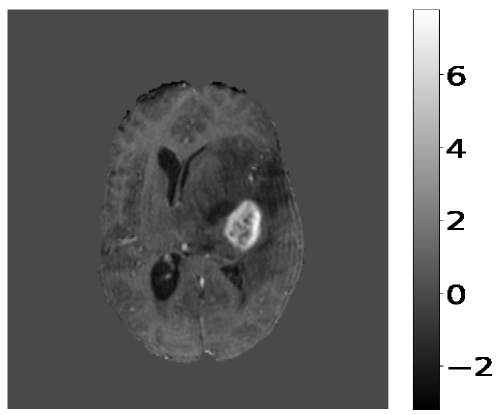

The pre-processing steps on the input MR image and target images are pre-requisites before training the deep learning model. Z-score normalization scales the pixel intensity values of the input MR image to have a mean of zero and a standard deviation of one, and is shown in Figure 2. It is a standard technique in medical imaging to account for variations in image acquisition parameters and to ensure consistent pixel intensity values across different images. The z-score normalization is applied only to brain tissue regions in the MR images, the rest remain unchanged.